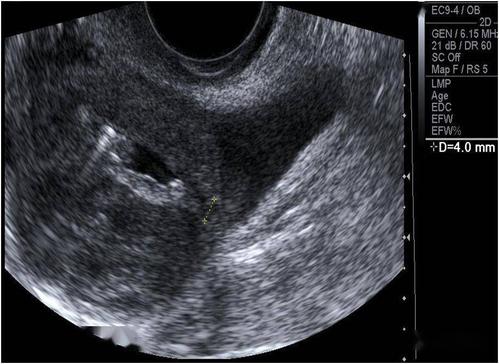

超声典型病例子宫穿孔

超声典型病例:子宫穿孔

子宫穿孔超声表现图

子宫穿孔超声图片

子宫穿孔彩超下表现